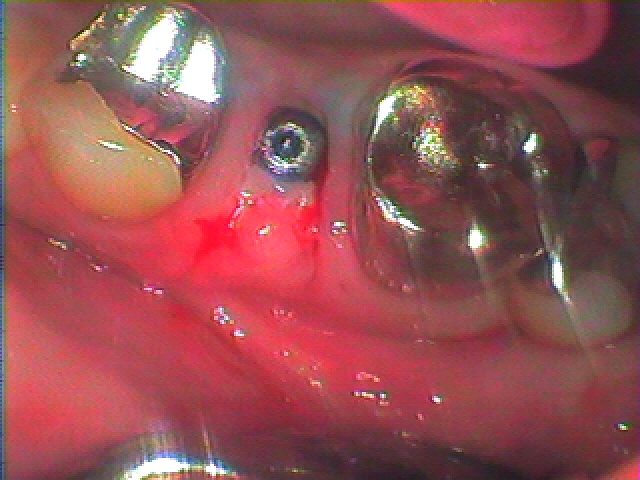

1週後には抜糸を行いました

1週後になります